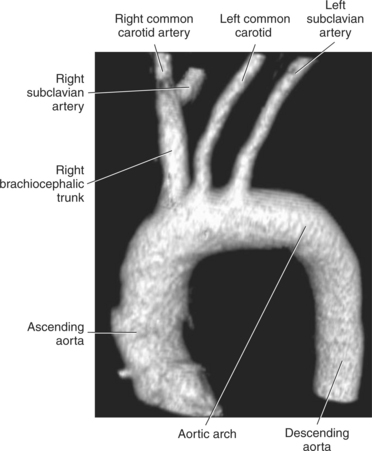

Blood travels to and from the heart through the great vessels, which include the aorta, pulmonary arteries and veins, and superior and inferior venae cavae (Figures 6.54 and 6.55). The aorta is the largest artery of the body and can be divided into the ascending aorta, aortic arch, and descending aorta. The ascending aorta begins at the base of the left ventricle at the level of the sternal angle, then curves superiorly and posteriorly as the aortic arch over the root of the left lung. The top of the aortic arch is approximately at T3 (Figures 6.56 and 6.57). The arch continues as the descending aorta posterior to the left bronchus and pulmonary trunk, on the left side of the vertebral body of T4 (Figures 6.58 and 6.59). The descending aorta passes slightly anterior and to the left of the vertebral column as it descends through the thoracic and abdominal cavities (Figure 6.60). While in the thoracic cavity, the descending aorta is commonly called the thoracic aorta, and while in the abdominal cavity, it is called the abdominal aorta. The pulmonary trunk is the origin of the right and left pulmonary arteries and lies entirely within the pericardial sac. It arises from the right ventricle and ascends in front of the ascending aorta, courses posteriorly and to the left, where it bifurcates at the level of the sternal angle (T4) into the right and left pulmonary arteries (Figures 6.61 through 6.63). The pulmonary trunk is attached to the aortic arch by a fibrous cord called the ligamentum arteriosum, the remnant of an important fetal blood vessel (ductus arteriosus) that links the pulmonary and systemic circuits during fetal development (Figures 6.54 and 6.61). The right pulmonary artery courses laterally, posterior to the ascending aorta and superior vena cava, and anterior to the esophagus and right mainstem bronchus, to the hilum of the right lung. At the root of the right lung, the right pulmonary artery divides into two branches, with the lower branch supplying the middle and inferior lobes and the upper branch supplying the superior lobe (Figures 6.61 through 6.64). The left pulmonary artery, shorter and smaller than the right, is also the most superior of the pulmonary vessels. It travels horizontally, arching over the left mainstem bronchus, and enters the hilum of the left lung just superior to the left mainstem bronchus (Figures 6.61 through 6.64). Within the lungs, each pulmonary artery descends posterolateral to the main bronchus and divides into lobar and segmental arteries, continuing to branch out and to follow along with the smallest divisions of the bronchial tree (Figures 6.61 and 6.64). Located inferior to the pulmonary arteries are the four pulmonary veins, two each (superior and inferior) extending from each lung to enter the left atrium (Figures 6.54, 6.55, 6.61, and 6.64 through 6.68). They commence in a capillary network along the walls of the alveoli, where they are continuous with the capillaries of the pulmonary arteries. The venous capillaries merge to form small vessels that unite successively to eventually form a single trunk for each lobe: three for the right and two for the left lung. Frequently the trunk from the middle lobe of the right lung unites with the trunk from the upper lobe, forming just two trunks on the right side prior to entering the left atrium. The right superior pulmonary vein collects blood from the upper lobe segments of the right lung and passes anterior and inferior to the right pulmonary artery, behind the superior vena cava. The right inferior pulmonary vein receives blood from the right lower lobes of the lung and crosses behind the right atrium to the left atrium (Figures 6.61 and 6.69 through 6.71). The left superior pulmonary vein receives blood from the left upper lobe of the left lung and courses anterior and inferior to the left main bronchus as it enters the left atrium. The left inferior pulmonary vein drains the inferior lobe of the left lung and passes toward the left atrium anterior to the bronchi (Figures 6.61 and 6.72 through 6.74). The pulmonary veins course more horizontally than the pulmonary arteries and are ultimately oriented toward the left atrium. At the root of the lungs, the pulmonary veins are anterior to the pulmonary arteries, which are anterior to the bronchus. While within the lungs, the branches of the pulmonary arteries are anterior to the bronchi, which are anterior to the pulmonary veins. The superior and inferior venae cavae are the largest veins of the body. The superior vena cava is formed by the junction of the brachiocephalic veins, posterior to the right first costal cartilage, and carries blood from the thorax, upper limbs, head, and neck (Figure 6.24). As it travels inferiorly, it is located posterior and lateral to the ascending aorta before entering the upper portion of the right atrium (Figures 6.54 through 6.59). The inferior vena cava is formed by the junction of the common iliac veins in the pelvis and ascends the abdomen to the right of the abdominal aorta and anterior to the vertebral column. It passes through the caval hiatus of the diaphragm and almost immediately enters the inferior portion of the right atrium (Figures 6.75 and 6.76).

The three main branches of the aortic arch are the brachiocephalic trunk, left common carotid artery, and left subclavian artery (Figure 6.84). The brachiocephalic (innominate) trunk is the first major vessel and the largest branch arising from the aortic arch. It ascends obliquely to the upper border of the right sternoclavicular joint, where it divides into the right common carotid and right subclavian arteries (Figures 6.85 and 6.86). The right common carotid artery ascends the neck lateral to the trachea to the level of C4, where it divides into the right external and internal carotid arteries. The right subclavian artery curves posterior to the clavicle into the axillary region, where it becomes the right axillary artery. The left common carotid artery is the second vessel to branch from the aortic arch. It arises just behind the left sternoclavicular joint and ascends into the neck along the left side of the trachea to the level of C4, where it bifurcates into the left external and internal carotid arteries. The left subclavian artery arises from the aortic arch posterior to the left common carotid artery and arches laterally toward the axilla in a manner similar to that of the right subclavian artery, where it continues as the left axillary artery (Figures 6.85 through 6.88). The right and left internal thoracic arteries arise from the respective subclavian artery at the base of the neck. They run deep to the ribs, just lateral to the sternum, to supply blood to the anterior portion of the thorax (Figure 6.89). The common carotid arteries supply blood to the head and neck, whereas the subclavian arteries supply blood to the upper extremities.